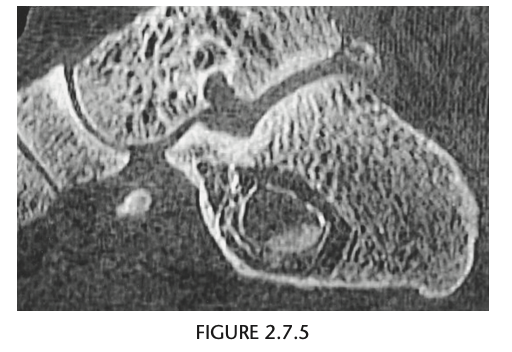

Foot pain

A lateral radiograph of the left foot demonstrates a prominent talar beak

­ (arrow) and bony sclerosis overlying the middle

facet (arrowheads). Coronal CT through the middle

facet shows talocalcaneal fusion, with bony bridging between the talus and the sustentaculum tali of the

calcaneus

Diagnosis: Tarsal coalition

abnormal fusion

of one or more of the tarsal bones, may be fibrous,

cartilaginous, or osseous and may be posttraumatic, or congenital.

Most

common tarsal coalitions are calcaneonavicular and

talocalcaneal.

Radiographically, calcaneonavicular coalition may

be suspected because of elongation of the anterior

facet of the calcaneus on radiographs (i.e., anteater

sign. CT can also be used to confirm coalition and shows

­ sclerosis at the articulation

Congenital coalition usually evolves from fibrous to osseous

coalition and may not be apparent on the initial

evaluation

Talocalcaneal coalition can result in dorsal beaking

of the talar head (Fig. 2.3.6, arrowhead), the so-called

C-sign (arrows)